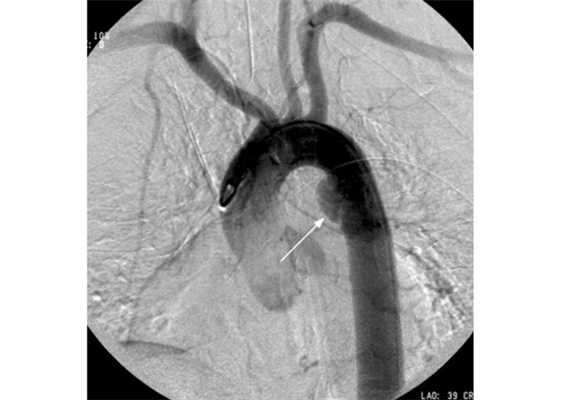

- Аортография - визуализация самой крупной артерии с помощью введения контрастного вещества непосредственно в сосуд, что очень информативно. Помимо структуры, можно оценить проходимость аорты, выявить аневризмы и пристеночные тромбы на всем ее протяжении.

Пример аортографии. Стрелкой указано мешковидное выпячивание (аневризма)